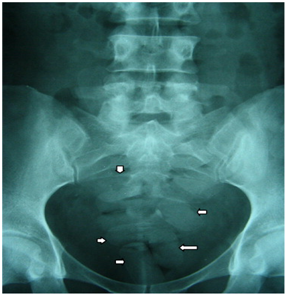

There are two potential pathways when an asymptomatic body packer arrives at hospital. For co-operative patients, those who have voluntarily presented themselves, or perhaps those who were coerced into couriering the drugs; they will undergo a physical examination and radiography to confirm their condition.5 Those who are non-cooperative (arrested) have the right to refuse treatment and examination, but they will be kept within the hospital and treated with laxatives and fluid diets until the packers spontaneously pass the packets.5 The radiography stage is imperative for any patient admitted who requires surgical treatment. “Radiological assessment is not only limited to the identification of packets but must also provide precise information about their number and exact location, both to ensure that none remains before the release of the suspect to the legal authorities and to recognize mechanical or systemic complications induced by the drug-filled ingested packets or their rupture”.50 “In the radiological report, it is… essential to specify the exact location of the packages in case of emergency surgical treatment reserved for the life-threatening complications of drug-packet ingestion”.51 However, radiology is not infallible, and there can be a problem with false negatives.49 Computer Tomography (CT) scanning can be used as a specific and sensitive method of Cocaine packaging identification.50,52 “Unenhanced CT is generally sufficient to identify the packets and their number and exact location”.50,52 This can also be used to locate ruptured packages due to the difference in density and irregularity in shape, with comparison to bowel contents etc.50 Once the patient’s status as a body packer has been confirmed and the location of the packages has been determined, the condition of the packer can be properly assessed Figure 9.5,53

Figure 9 “Plain abdominal radiograph showing several cocaine pellets within the rectum and sigmoid colon (arrows)”.5